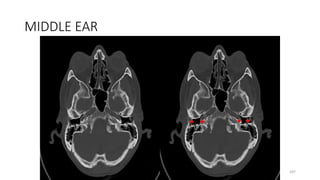

MIDDLE EAR

187

202

MIDDLE EAR WITH MALLEUS AND INCUS

214

224